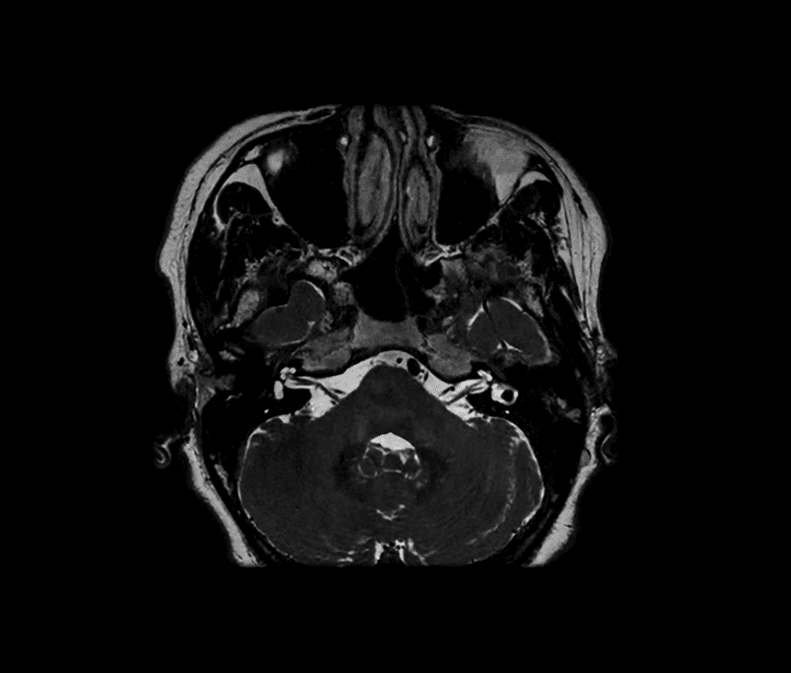

Eksempler på MR-scanninger

- Hjerne, rygmarv og hele rygsøjlen (centralnervesystemet)

- Bihuler, ører og hals